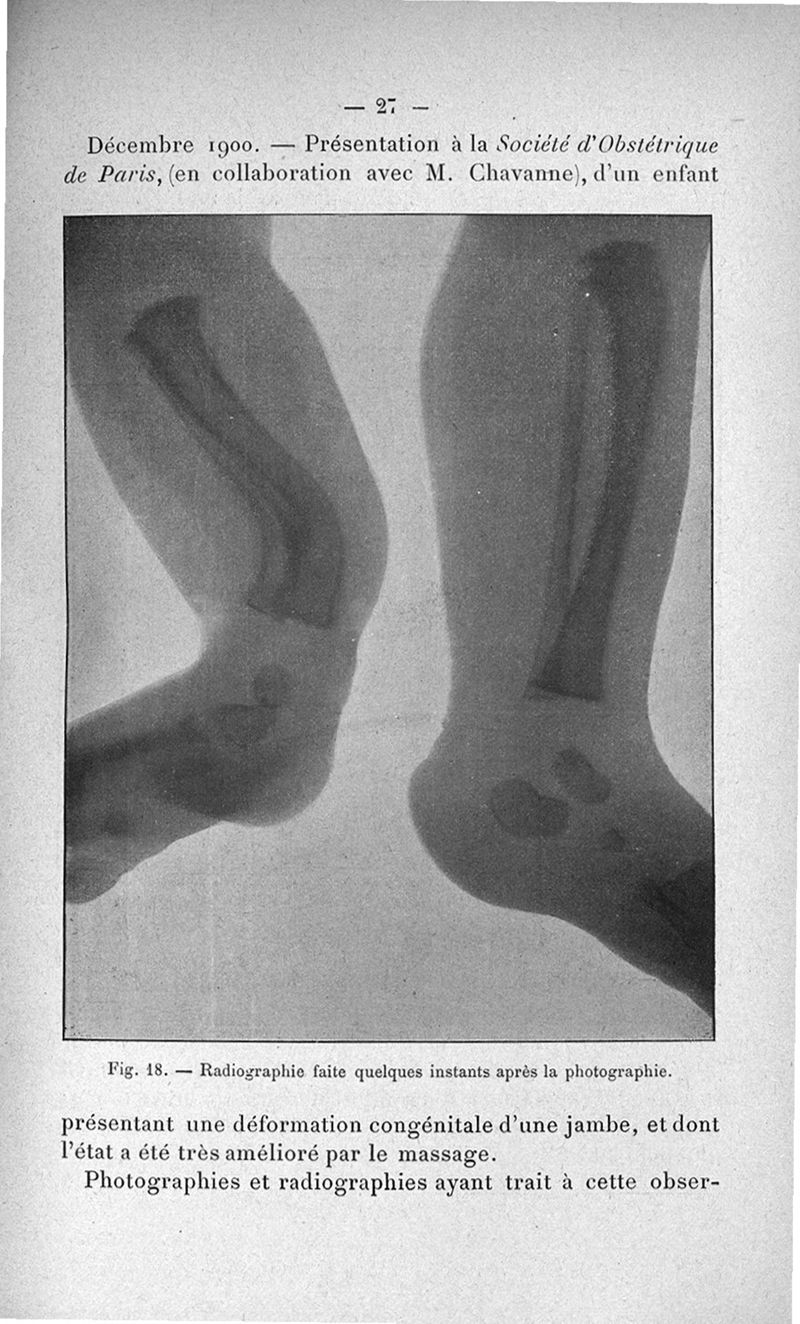

Titres scientifiques du Dr L. Bouchacourt, agrégation de chirurgie, section d'accouchements, concours de 1901 comprenant un mémoire de 11 p. présenté à la Société d'obstétrique